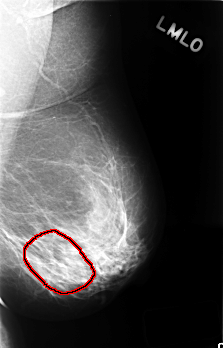

C_0405_1.LEFT_MLO

LEFT_MLO LINES 4512 PIXELS_PER_LINE 2888 BITS_PER_PIXEL 12 RESOLUTION 50 OVERLAY

FILE: C_0405_1.LEFT_MLO.OVERLAY

TOTAL_ABNORMALITIES 1

ABNORMALITY 1

LESION_TYPE CALCIFICATION TYPE AMORPHOUS DISTRIBUTION SEGMENTAL

ASSESSMENT 4

SUBTLETY 1

PATHOLOGY BENIGN

TOTAL_OUTLINES 1

BOUNDARY